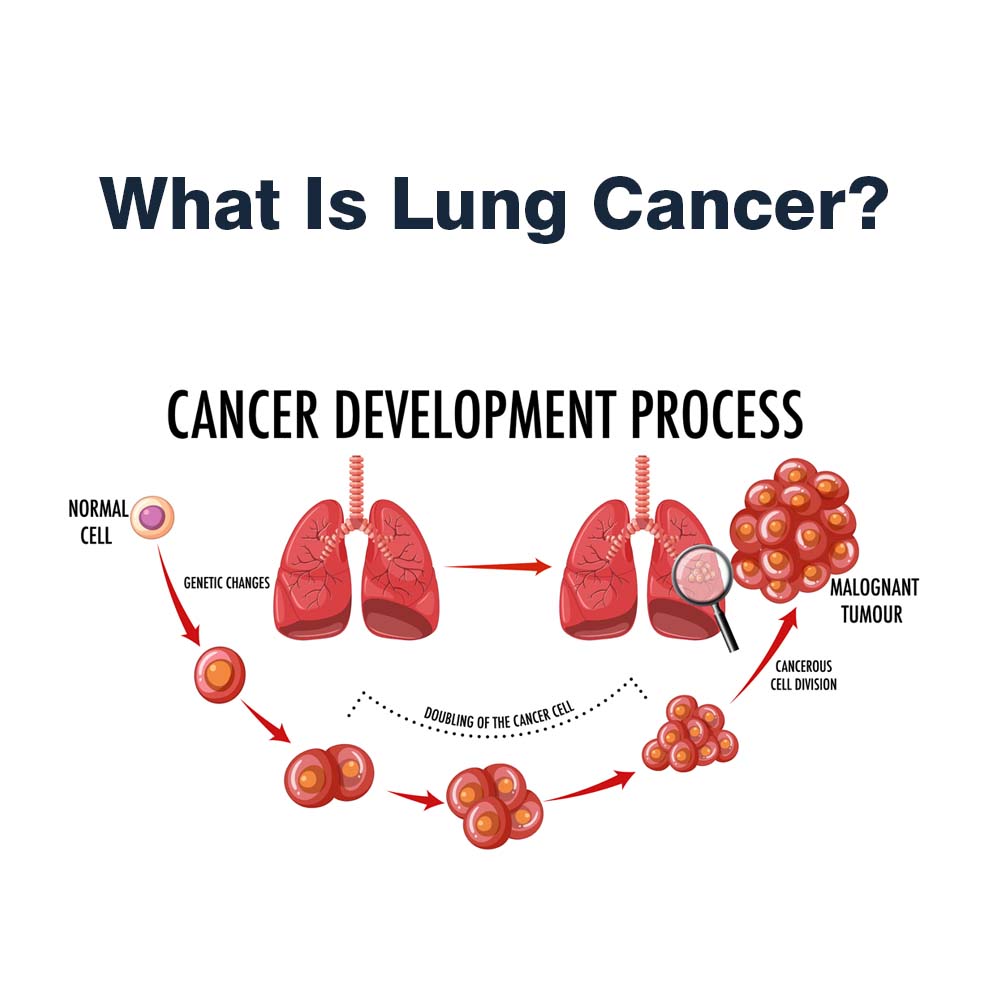

Lung cancer is cancer that starts in your lungs. The most important thing you can do to prevent lung cancer is to not start smoking, or to quit if you smoke. Lung cancer patient and advocate jill feldman takes pills at home that shrink tumors by blocking a signal that tells cancer cells to grow.

Avoiding things known to cause cancer. Learn what lung cancer is, what the symptoms are, how to lower your risk, and who should be screened for lung cancer. Advances in treatments have caused a.